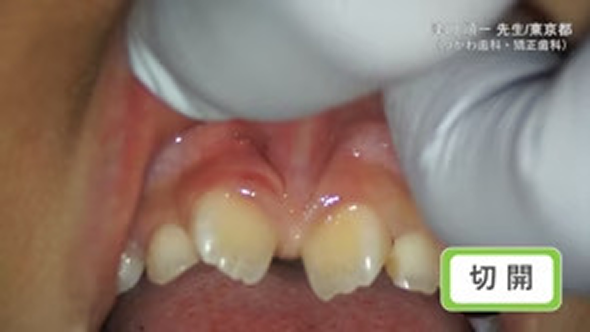

臨床例:半導体レーザーFilioを使用した先生の臨床例です。

切開